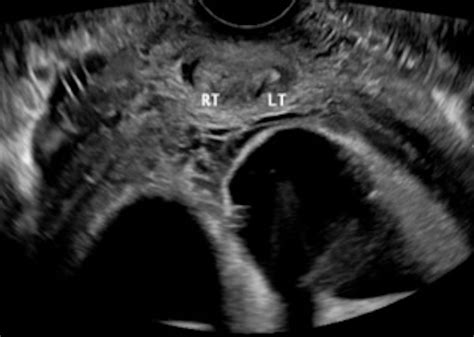

Physicians use advanced imaging to confirm the diagnosis. If you are looking at Didelphic Uterus Images for reference, you will notice the clear separation of the two uterine horns. Common diagnostic tools include:

Transvaginal Ultrasound Initial screening and visualization High for initial detection

When analyzing Didelphic Uterus Images in a medical context, notice how the dual cervixes are positioned. This is a critical detail for healthcare providers during cervical cancer screenings (Pap smears) or during labor and delivery, as each side needs to be assessed independently.